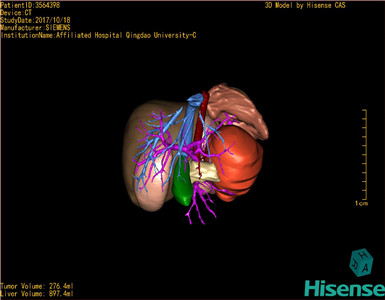

CT结果输入海信CAS系统后行3D重建及手术规划后,于2017-10-19全麻下行“胰体尾肿物切除术+脾切除术+大网膜切除术”手术治疗:

术前三维重建及手术方案设计:

将0.625mm双源薄层CT资料的静脉期和动脉期Dicom格式文件导入海信CAS系统。

通过调节窗宽窗位调整CT序号,对肝实质,胆囊,下腔静脉,肿瘤,肝动脉、门静脉及肝静脉等进行三维重建;系统自动计算肝脏体积。

模拟手术操作,自动计算切除肿瘤体积。肝脏体积为453.7ml,通过比对2-3岁正常肝脏体积为475.97±99.7ml,通过术前模拟手术,精准判断切除后剩余肝脏体积能耐受,避免肝衰竭发生。

术前三维重建:

重建图片